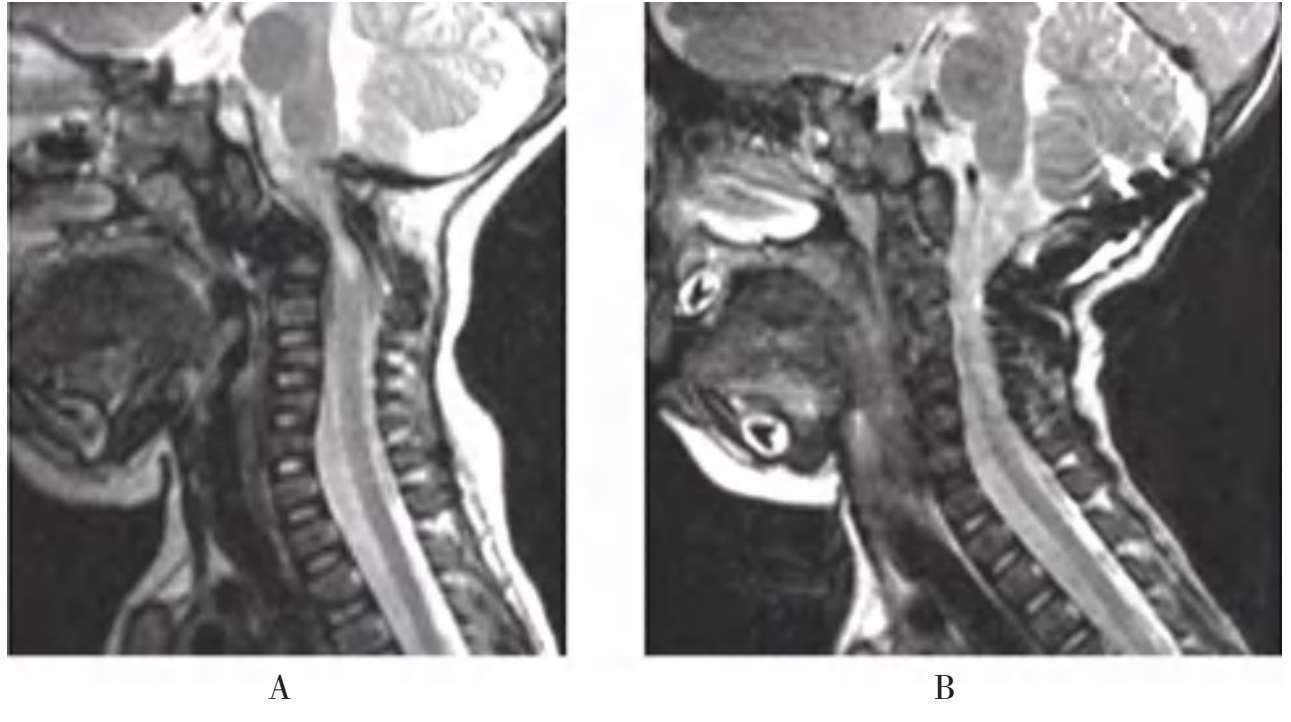

A.术前;B.术后

图1-31 典型病例介绍,术前、术后核磁共振对比,患儿脊髓压迫解除